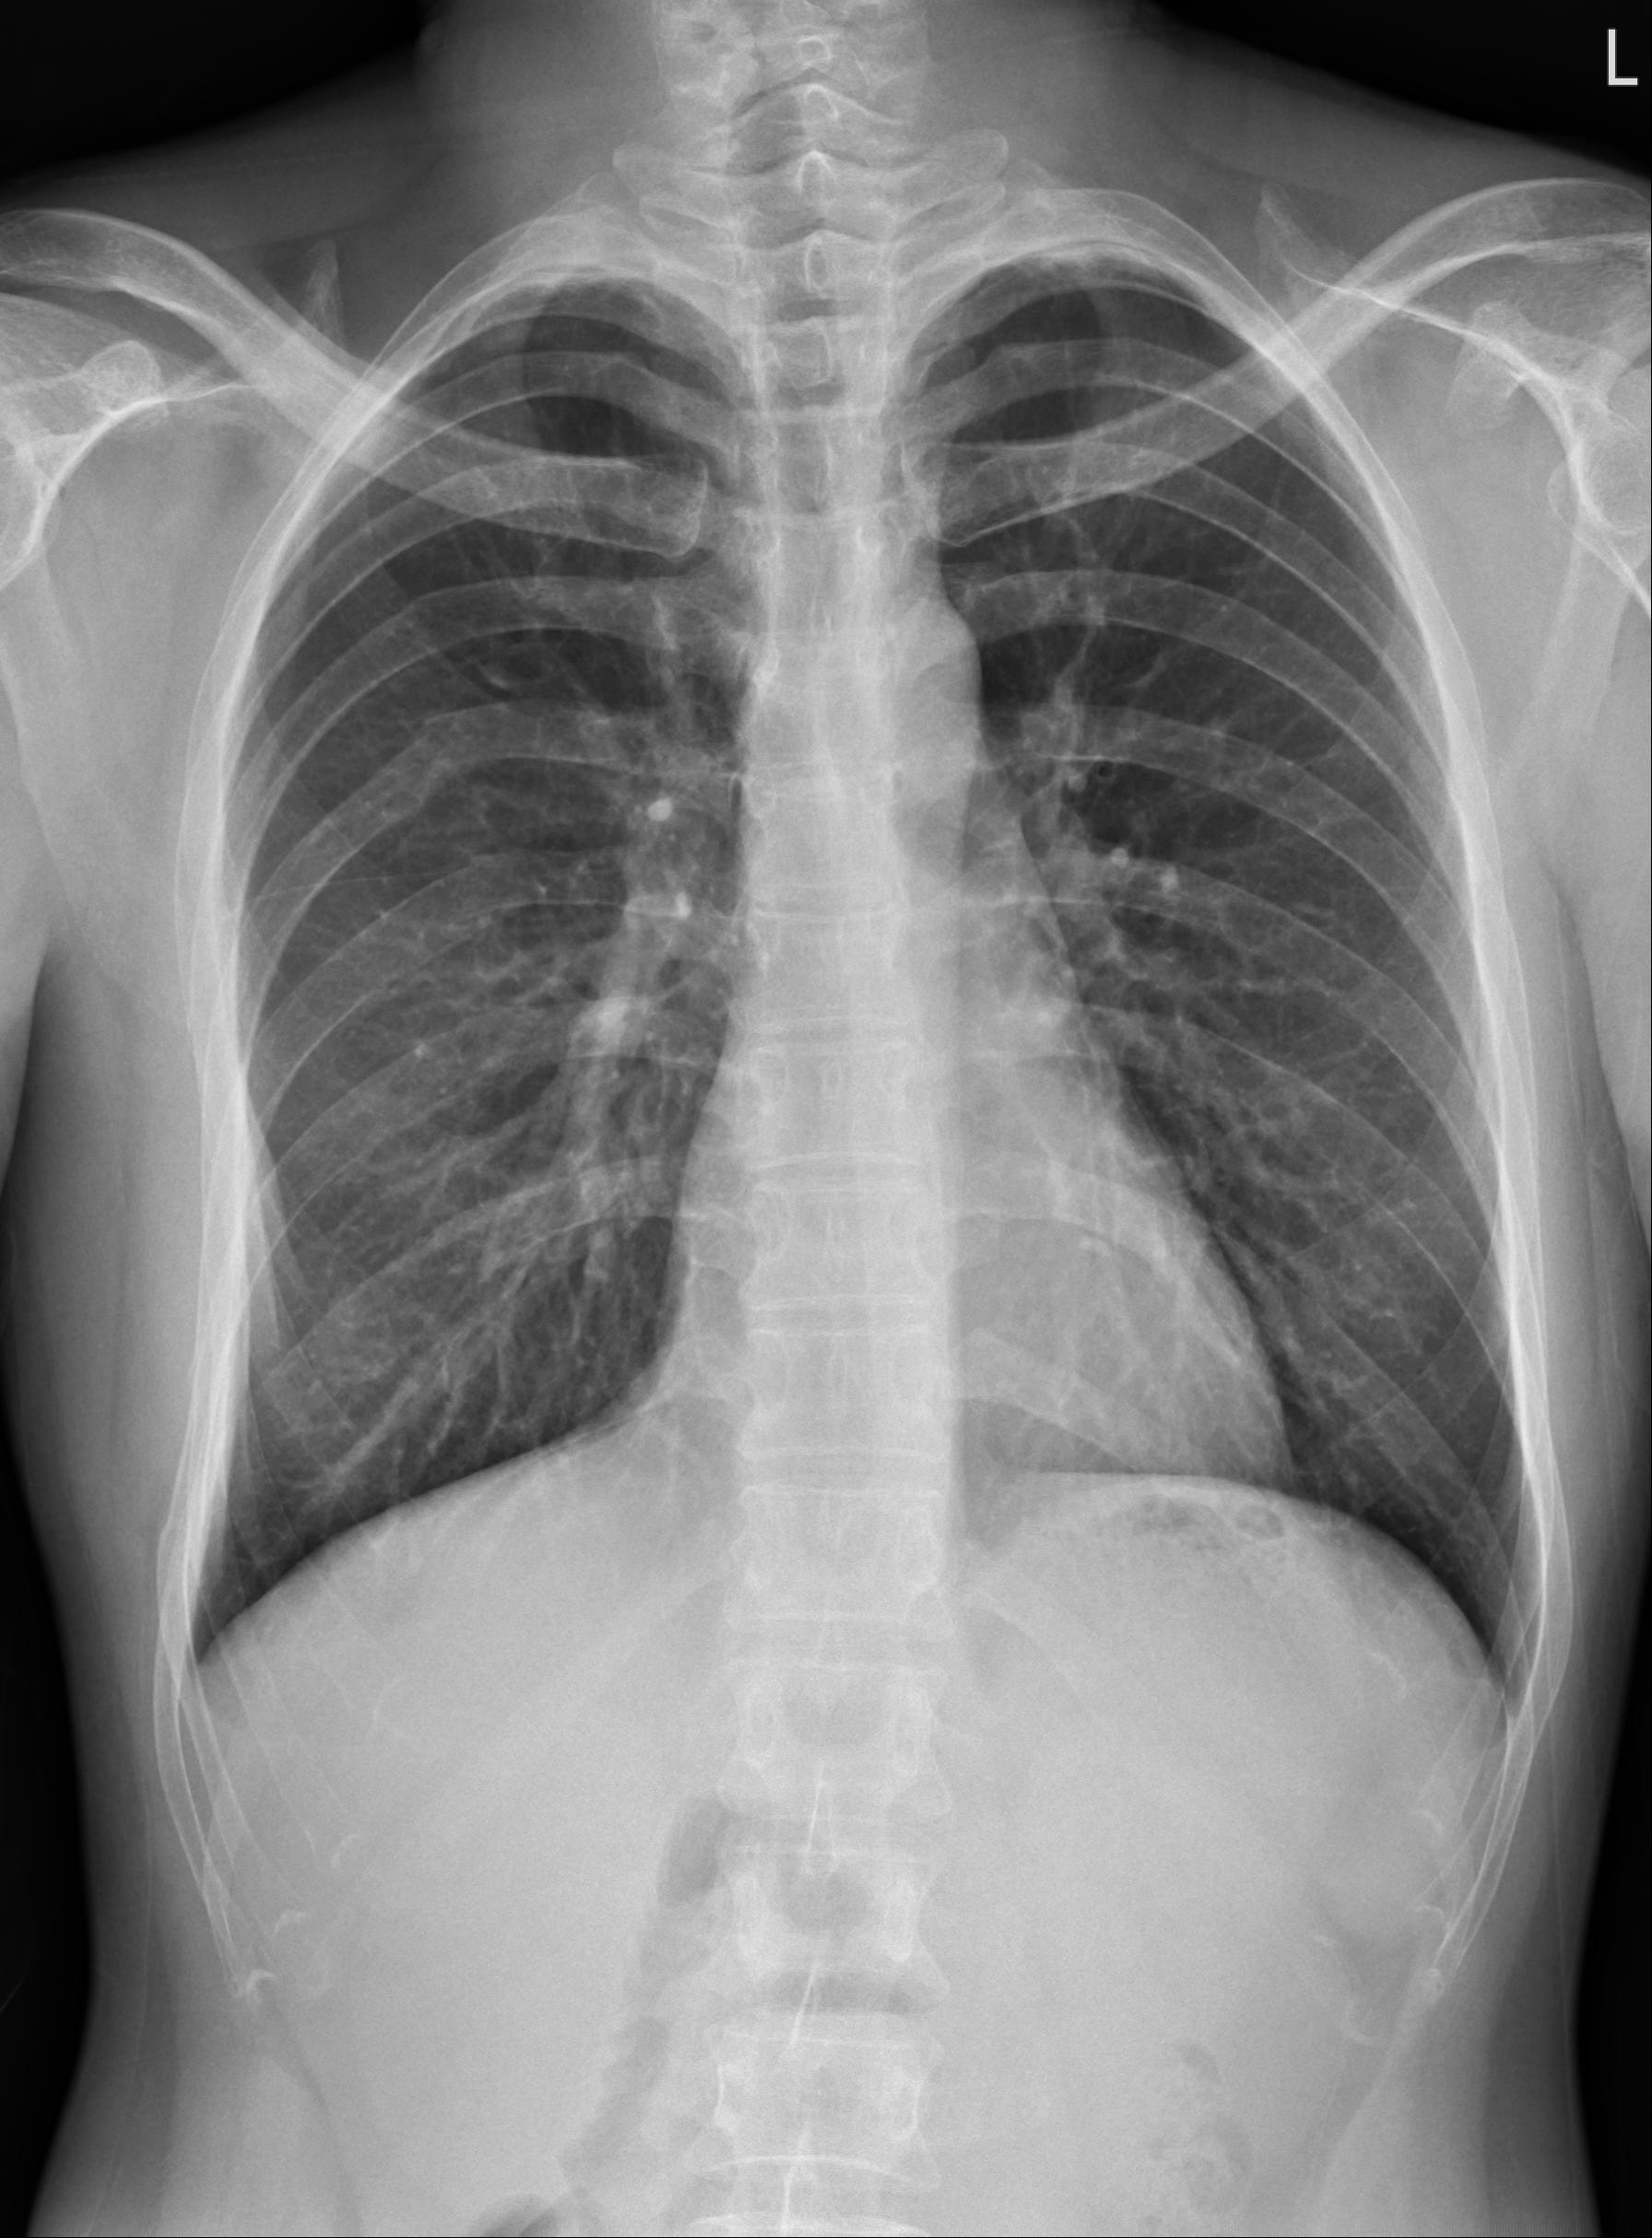

CXR可見右側胸部多處肋骨骨折。

年輕男性,機車車禍,除四肢多處擦傷,還主訴右側胸痛

生命徵象穩定,無呼吸困難,但有明顯壓痛。